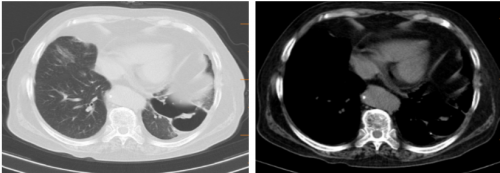

随访11-17胸部CT:

随访12-16胸部CT: